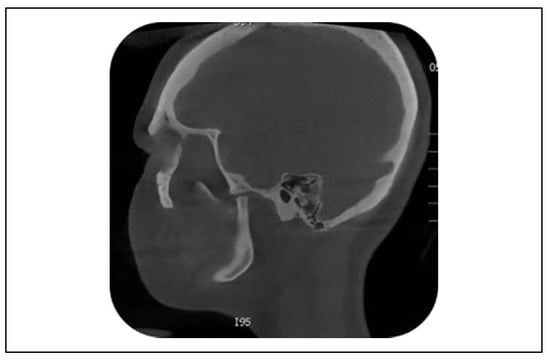

Reduced mouth opening is a complaint in 8-10% of all condylar fractures and is usually present immediately after trauma but can persevere and worsen over time. Early mobilization should be considered to avoid reduced mouth opening, even at the expense of a stable occlusion.[16,17] The longer the period of IMF, the more hypo-mobility is described.[13] Different causes of reduced mouth opening as a long-term complication have been described, including intracranial condyle, condylar sag, condylar resorption, bifid condyle, non-union, and ankylosis. An intracranial condyle is a rare condition caused by a high energetic trauma. A literature review revealed 51 previous cases in the English language.[18] Condylar sag was first described by Hall in 1975 and can be described as a change in the position of the condyle in the glenoid fossa after establishing a proper occlusion.[19,20,21] In 1 patient suffering from reduced mouth opening, condylar sag was thought to be the cause (Figure 1 and Figure 2).

Figure 2. Condylar sag of the left condyle, cone beam computed tomography.